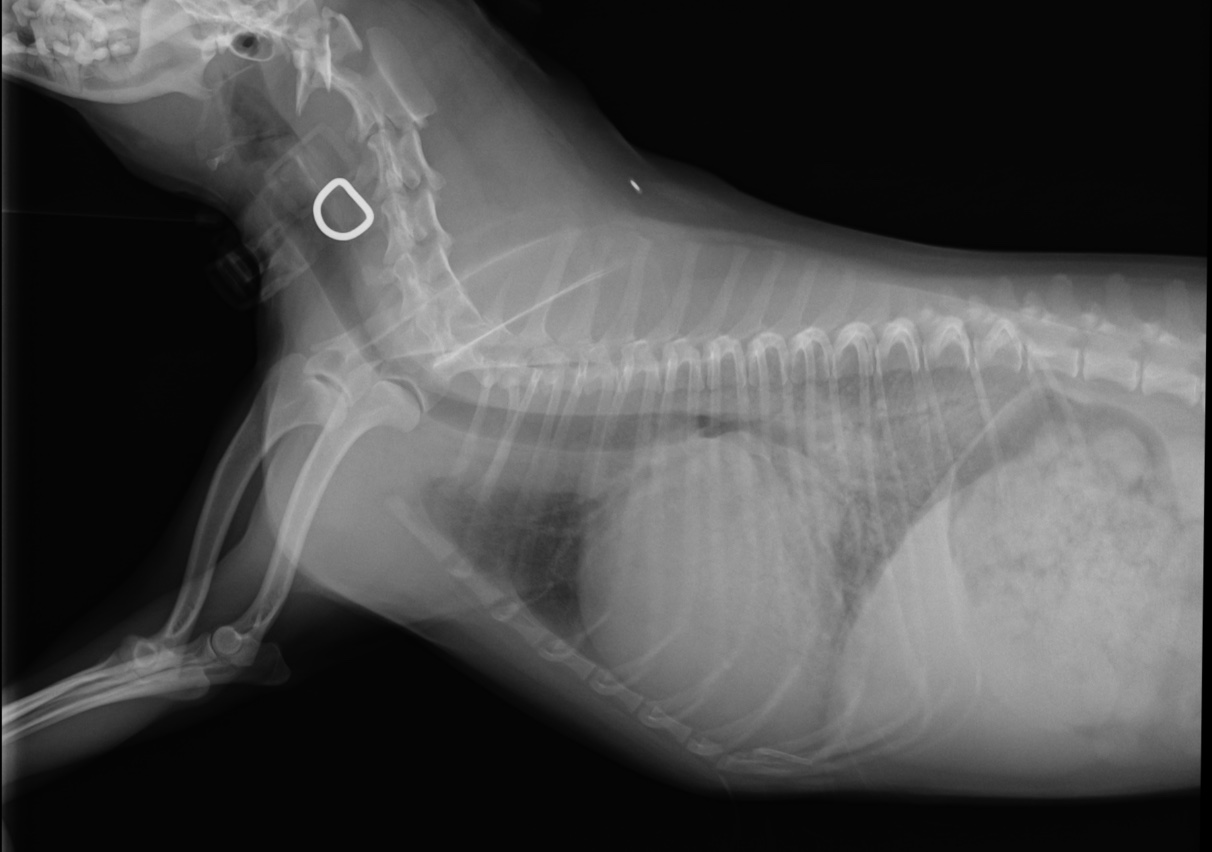

手術前

■ 検査所見

心臓超音波検査では、

• LA/Ao:2.70

• LVIDDN:2.37

• 重度僧帽弁逆流

を認め、左房・左室ともに著明な拡大が確認されました。